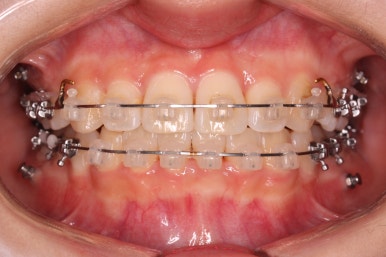

위 사진은 연산동교정치과 처음 내원하셨을 때의 입안 모습입니다. 몇 가지 모습이 관찰됩니다.

치아가 삐뚤삐뚤합니다.

위~아래 앞니가 많이 겹쳐서 아랫니가 많이 모이지 않는 "과개교합" 입니다.

앞니가 앞으로 뻐뜨러져 있습니다.

우선 윗니부터 가지런하게 합니다. 그리고 아랫니는 가지런하게 할 준비를 하죠.

아랫니에도 이제 장치를 붙였습니다.